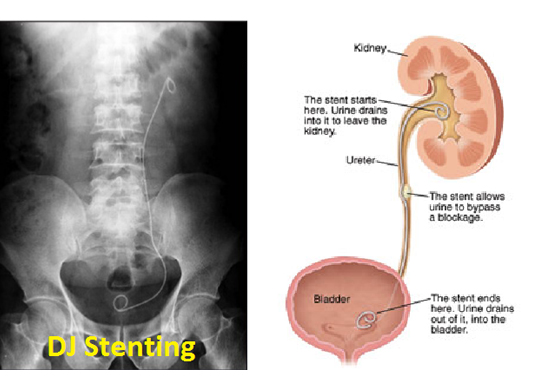

Blood is filtered in the kidneys and urine is formed. The urine formed in the kidneys passes to the urinary bladder through the ureters. When there is a block in the path along the ureter, urine stagnates. This urine stagnation has two adverse effects – it damages kidneys and stagnant urine predisposes to infection. The block has to be relieved as early as possible. This is done by the urologists from below under general anaesthesia. In patients where this is not successful or the general condition of the patient is not suitable for general anaesthesia the block can be bypassed from above by an interventional radiologist. This process called “percutaneous nephrostomy” can be done under local anaesthesia. A tube called catheter is placed through which the urine comes out of the body into a collecting bag placed outside the body. A stent can also be placed in the ureter so that urine formed proximal to the block bypasses the block and enters the urinary bladder, this process is called ‘antegrade ureteric stenting’. Similar blocks in the outflow of the urinary bladder can be relieved by percutaneous cystostomy till the permanent treatment is done.

Blood is filtered in the kidneys to form urine. Urine then moves along a passage called the collecting system which includes ureters and urinary bladder. When this pathway is obstructed due to any reason urine is retained within the system and pressures builds up. This raise in pressure hinders normal functioning of kidneys and it fails. The retained urine could get infected. The treatment involves removing the obstruction when possible. In cases where removal of the cause is not immediately possible the urine can be temporarily diverted out of the body by placing a tube through the skin. This procedure is called percutaneous nephrostomy. If possible a stent can be placed across the obstruction with one end above and the other end below the obstruction. This procedure is called DJ stenting. Both these procedures are done under local anaesthesia and are life saving many a times. Similarly a tube can be placed in the urinary bladder through the skin when its outflow is obstructed and this procedure is called percutaneous cystostomy.